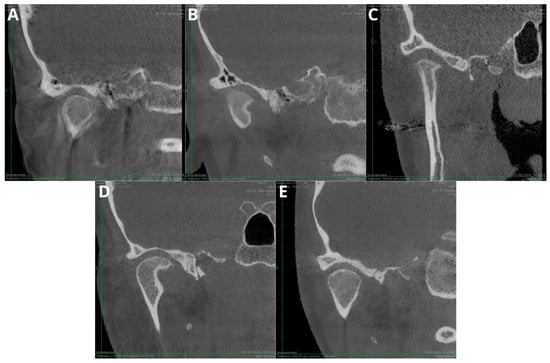

2.5. Lesion Assessment

- flattening—the loss of the convex form of the articular surface;

- erosion and subchondral cysts—the loss of continuity in the cortical bone margins +/− cavities below the articular surface;

- osteophytes—marginal hypertrophy with sclerotic borders and the exophytic angular formation of the osseous tissue arising from the surface;

- subcortical sclerosis—an increase in the thickness of the cortical plate;

- condylar deformation—abnormal morphology of the condyle.